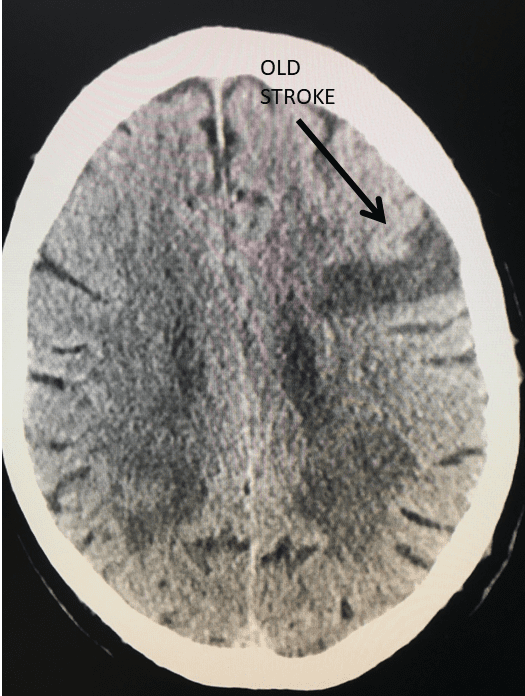

Figure 2.

Catheter angiography prior to angioplasty revealed critical stenosis (Figure 2). Angioplasty was therefore performed under local anesthesia with an embolic protection device deployed to catch any dislodged debris (Figure 3). After angioplasty, a stent was opened across the lesion to maintain long-term patency (Figure 4). Post-stent angiography showed smooth dilatation of the lesion. The patient’s aphasia continued to improve at his 6-week follow-up visit and duplex revealed no significant stenosis through the stent.